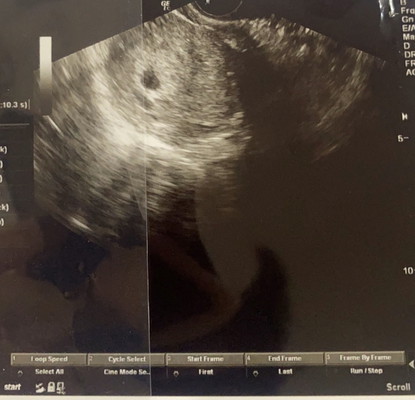

เราท้อง 5 วีคกว่าเจอแต่ถุง อีก 7 วันหมอนัดไปซาวอีก หมอบอกถ้ายังไม่เจอตัวอ่อนจะเป็นสัญญาณที่ไม่ดี หรือท้องลม เราหดหู่เลยคะ ?

ซาวด์ทางหน้าท้องหรือช่องคลอดคะแม่ ถ้าทางหน้าท้อง ถ้าตัวอ่อนยังเล็กมากๆ หรือเป็นคนหน้าท้องหนา อาจจะยังไม่เห็นค่ะแม่ ทางช่องคลอดจะพอมีลุ้นมากกว่าค่ะ ทั้งนี้เป็นไปได้ว่า อายุครรภ์อาจจะน้อยกว่าที่นับ เพราะไข่อาจจะตกช้ากว่ากำหนด ตัวอ่อนยังเล็กมากอยู่ จึงยังไม่พบ ก็เป็นได้ค่ะแม่ ทานโฟลิคทุกวัน พักผ่อนเยอะๆ นะคะ ซาวด์ครั้งหน้าอาจจะได้เจอกันแล้วจ้า